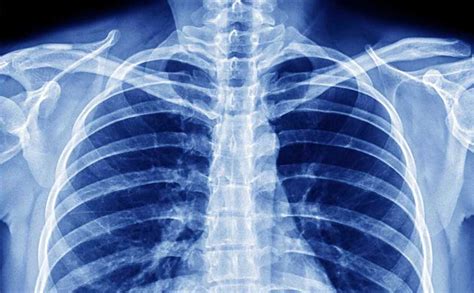

- Radiografia del torace: Questo è l'esame di primo livello per la diagnosi di polmonite. Permette di visualizzare il parenchima polmonare e identificare la presenza di focolai infiammatori, versamenti pleurici o altre anomalie. Viene generalmente eseguita in due proiezioni (antero-posteriore e latero-laterale). La lastra aiuta a confermare la diagnosi, soprattutto in casi dubbi, e a valutare l'estensione dell'infiammazione.

- Tomografia Computerizzata (TC) del torace: In caso di complicanze, diagnosi differenziale con altre patologie, o per ottenere immagini più dettagliate, può essere eseguita una TC torace. Offre una risoluzione elevata e immagini tridimensionali, ma è controindicata in gravidanza e da usare con cautela nei bambini.